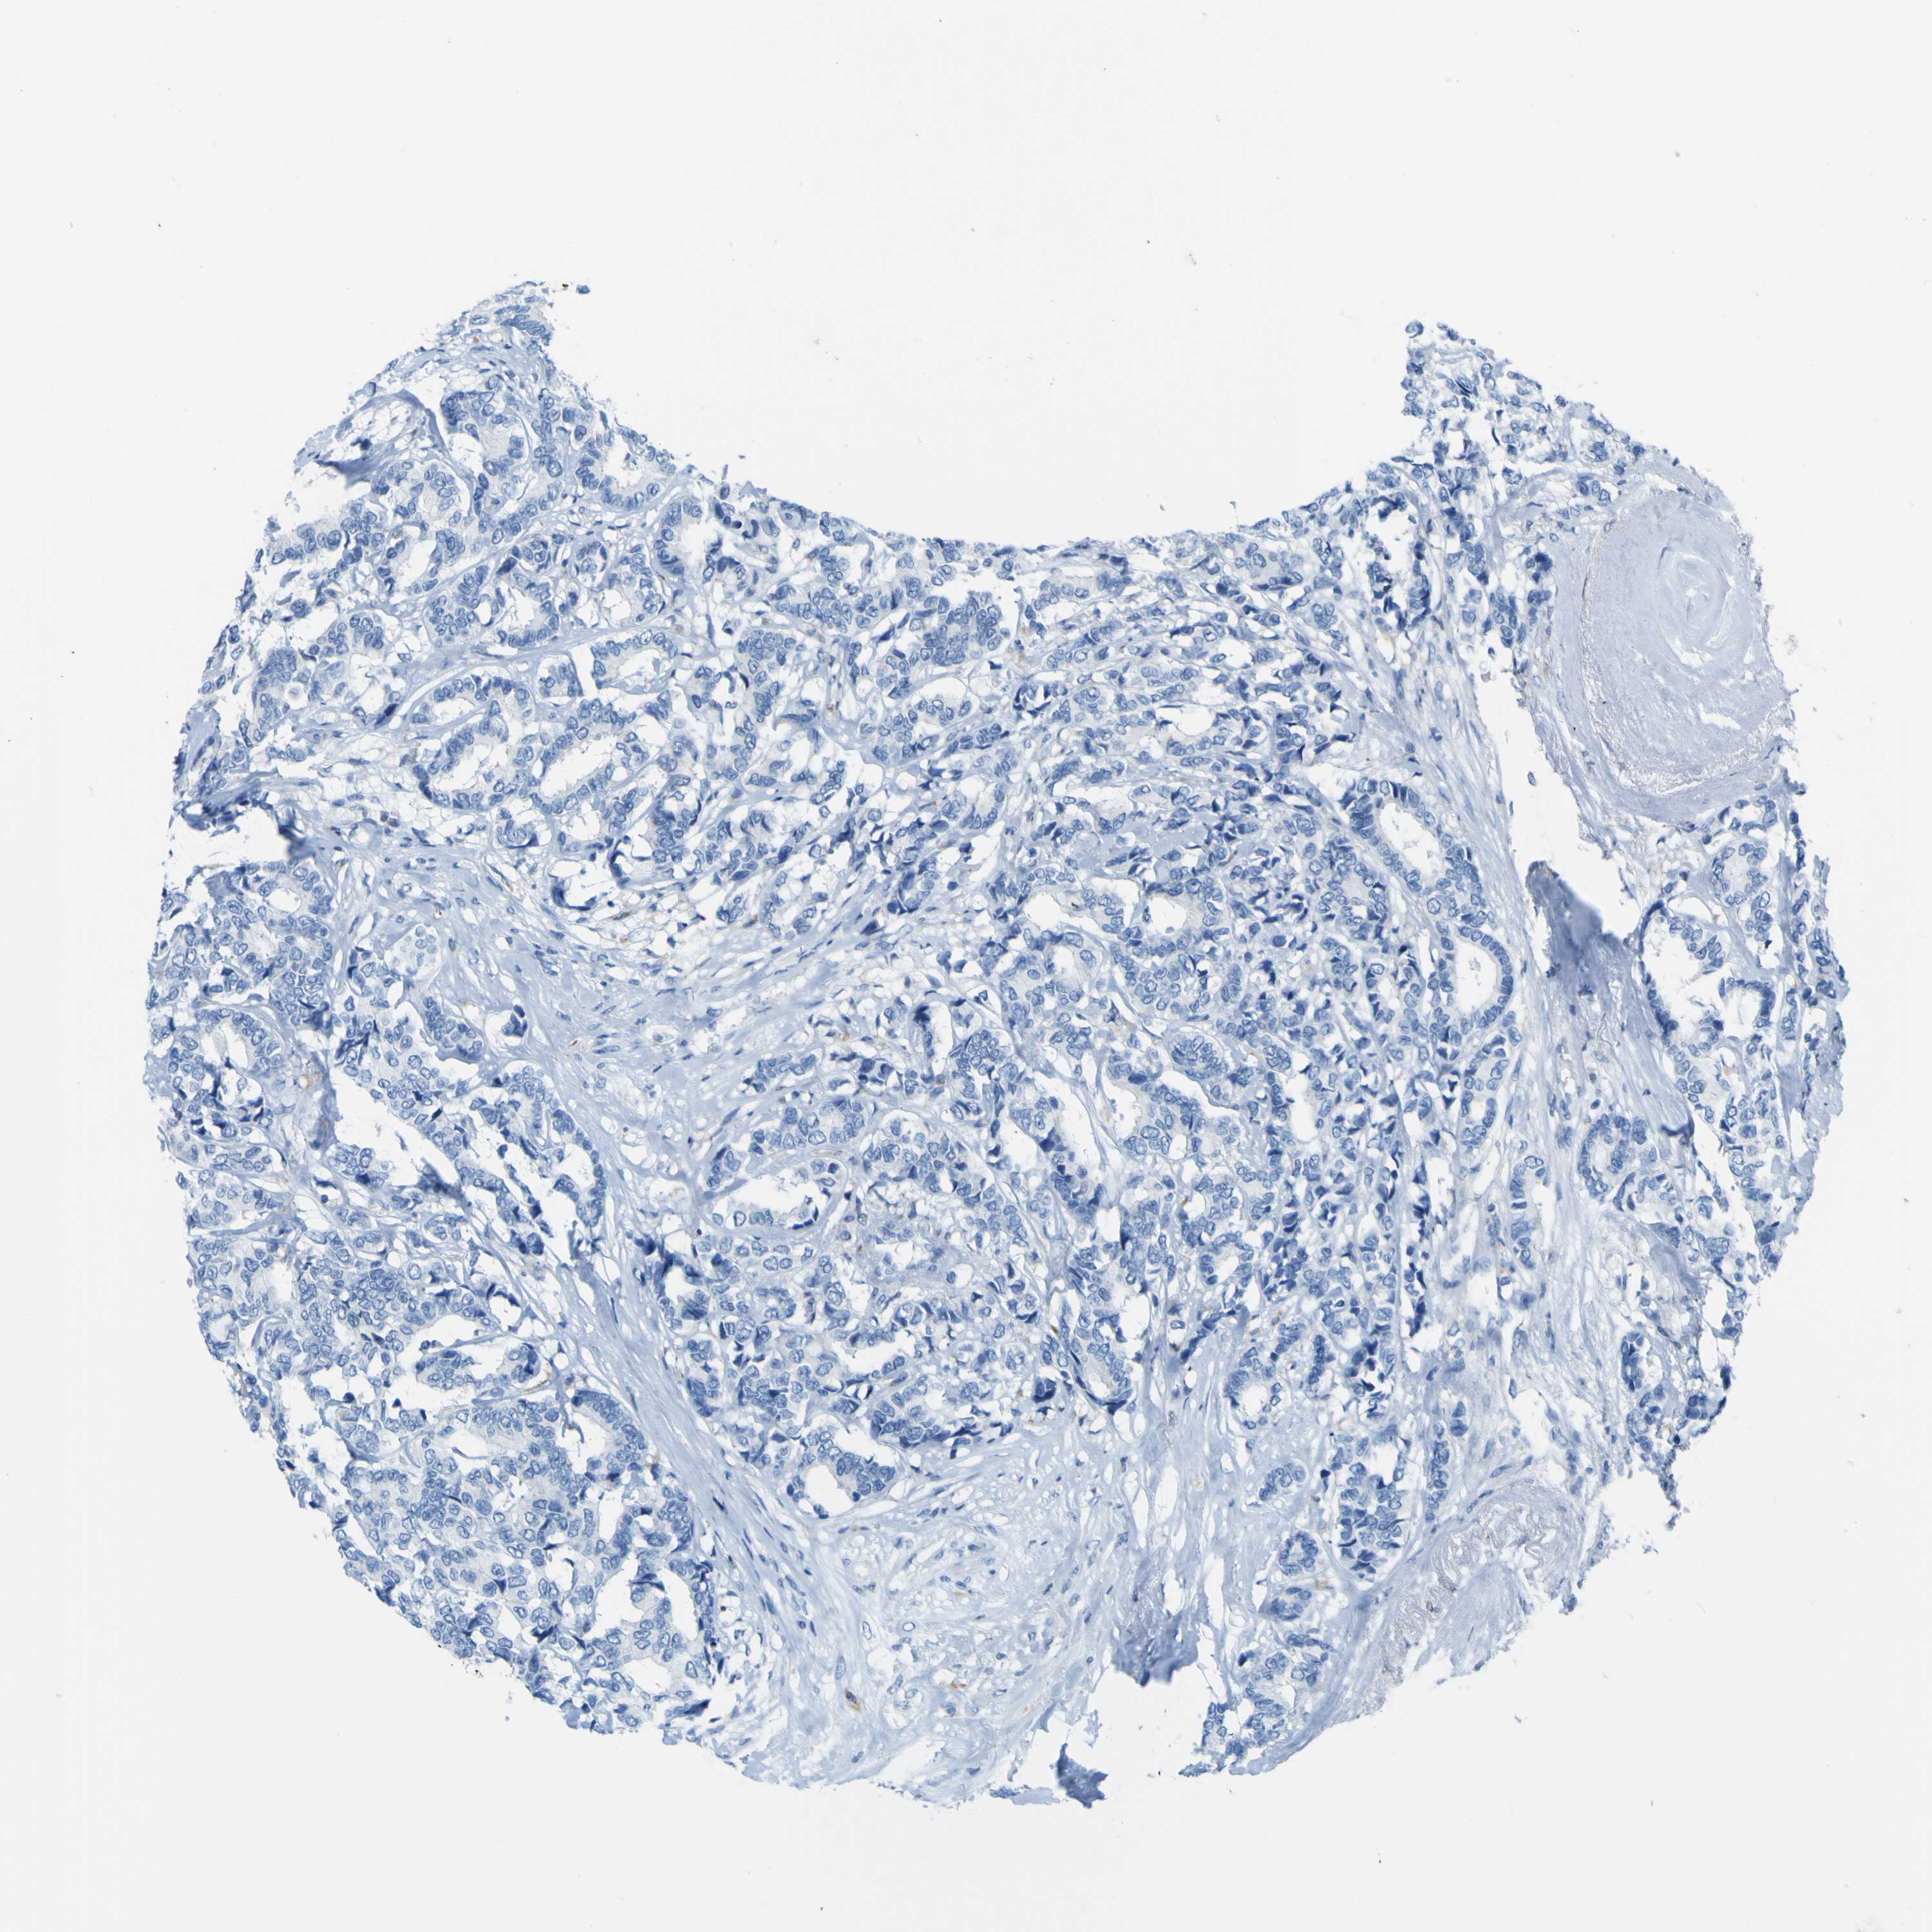

BRCA TCGA BRCA VALIDATION PROTEIN EXPRESSION

ANTIBODIES

AND

VALIDATION